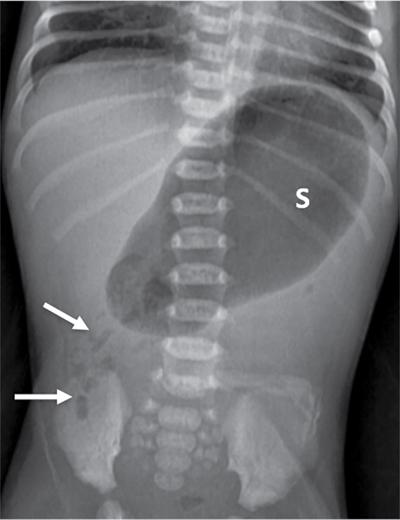

C.V. Kanimozhi, S. Muralinath, Raveendran J. Many of the important congenital gastrointestinal abnormalities present acutely in the newborn; some present much later. These include obstructive gastrointestinal lesions that present with vomiting, abdominal distension and not having passed meconium. The imaging modalities that are most commonly used in the evaluation of neonatal gastrointestinal abnormalities are plain films, contrast studies and ultrasound. Plain films remain a valuable tool in the assessment of abdominal abnormalities in the neonate. They are also an excellent guide to determining the next proper imaging study to perform for a particular problem. Certain neonatal bowel disorders have a pathognomonic appearance on radiographs obviating the need for further imaging. The essential and basic view to be done at the bedside is the supine view of the abdomen. In the evaluation of abnormal intra-abdominal gas patterns, alternative decubitus views, prone and supine cross-table lateral views may be taken. Erect view is not utilized in neonatal practice at the bedside as it is impossible to restrain a neonate in that position and unnecessarily subjects the neonate to stress, which may worsen the condition of an already sick baby. Evaluation of the bowel gas pattern and the anatomic localization of the intra-abdominal gas is the key to diagnosis in the evaluation of diseases of the GI tract. The bowel gas in the neonate is essentially swallowed air (Box 7.8.1). Movement of Air Through the GIT in a Term Neonate Most infants pass meconium by 24 hours of life. In order to interpret the bowel gas pattern and determine if an abnormality is present, it is crucial to know the age of the neonate (hours since birth) at the time the radiograph was taken. When there is impaired swallowing, such as due to CNS depression or in prematurity, radiographs show diminished bowel gas. In cases of bowel atresia, radiographs show absence of bowel gas in distal segments. Thus, the distribution of bowel gas and its pattern serve as pointers to the diagnosis. After the radiograph has been done, depending on the findings, an ultrasound or fluoroscopic contrast study may be performed next. The radiologist should tailor the contrast study to suit the particular patient and the clinical question that needs to be answered. In cases of suspected high GI obstruction, an upper GI contrast series is study of choice; in cases of suspected low GI obstruction a contrast enema should be performed to delineate the anatomy. When performing fluoroscopic studies, it is important to bear in mind the radiation dose and to adopt the ALARA principle. Minimizing radiation exposure in children is important because they are more sensitive to the effects of radiation and have a longer life expectancy than adults. The technical parameters must be adapted to paediatric imaging. Ultrasound is a useful bedside tool particularly in the sick neonate. In neonates, the sonographic image resolution is excellent due to the lack of significant body fat. In neonates, exquisite images of the abdomen can be obtained with the high-resolution ultrasound probe, which permits imaging the bowel wall in great detail. In addition, it can also reveal other causes for abdominal distension or vomiting. In this chapter, we will discuss the aetiology, clinical presentation and imaging appearances of congenital neonatal gastrointestinal abnormalities. We will also discuss common acquired abnormalities that present in the neonatal period, namely necrotizing enterocolitis. Congenital oesophageal malformations of the newborn include the various types of atresia (with and without fistula) and oesophageal duplications. Oesophageal atresia with or without tracheoesophageal fistula (TEF) is a common congenital anomaly that manifests in the neonatal period. It is also the most important congenital malformation of the oesophagus. Oesophageal atresia is commonly associated with other anomalies of the gastrointestinal tract such as imperforate anus, pyloric atresia, duodenal atresia and annular pancreas and less frequently with anomalies of the cardiac and genitourinary systems. About 20% of patients with oesophageal atresia have the VACTERL syndrome (vertebral anomaly, anorectal atresia, cardiac lesion, tracheoesophageal fistula, renal anomaly, limb defect). Oesophageal stenosis and webs may be associated with oesophageal atresia. The aetiology of oesophageal atresia and TEF is not completely understood. Faulty separation of the primitive trachea and oesophagus is the most widely accepted theory. The way the primitive foregut cleaves into a ventral (tracheal) passage and a dorsal (oesophageal) passage is a complex process and is poorly understood. Folds developing from the longitudinal ridge is said to separate the two. When the separation has an extreme tracheal bias, an oesophageal atresia occurs and if the bias is towards the oesophagus, then a tracheal atresia ensues. Incomplete separation may result in fistula of various types. Oesophageal atresia and TEF are classified depending upon the absence or presence and location of the fistula between the oesophagus and the trachea (Fig. 7.8.1). Neonates present within a few hours of birth with excessive salivation, drooling, cyanotic spells and regurgitation of feeds. The inability to successfully pass a nasogastric tube strongly suggests oesophageal atresia. Newborns with H-type fistula may have feeding difficulties and choking, but often the presentation and diagnosis is only later in infancy when the patient presents with cough, choking episodes and recurrent pneumonia. The role of imaging is to diagnose, define the anatomy to the best extent possible and evaluate for other anomalies to provide a clear picture for the paediatric surgeon. For example, it is important for the surgeon to know the side of the aortic arch in order to lateralize the surgical approach. Chest X-ray and Echo can localize the arch and determine if an anomalous right-sided aortic arch is present. Plain films of the chest including abdomen need to be obtained. The radiograph will demonstrate the air-filled distended proximal oesophageal pouch. If a nasogastric tube has been inserted, the coiled tube will be seen within the pouch. Absence of bowel gas in the abdomen indicates oesophageal atresia without a distal fistula – types A and B have this radiographic appearance (Fig. 7.8.2). The presence of gas in the gastrointestinal tract indicates the presence of a distal fistula – types C and D (Fig. 7.8.3). Contrast studies to delineate the proximal pouch are generally not indicated. Coiling of the nasogastric tube in the proximal pouch confirms the diagnosis. Chest radiographs frequently show changes of consolidation due to aspiration pneumonia, most often involving the right upper lobe (Fig. 7.8.4). In cases of H-type fistula, plain films are nonspecific and the diagnosis depends on contrast studies. Radiological diagnosis is made by means of a tube oesophagogram. This study has the potential risk of aspiration and the neonate may desaturate quite rapidly. Hence, it is important to have neonatal emergency resuscitation at hand. The tube oesophagogram is performed under fluoroscopy with the baby in lateral- or steep-prone oblique position. The NG tube is placed at the oesophagogastric junction and is gradually withdrawn while simultaneously injecting contrast. Nonionic low-osmolar contrast agent should be used. Most of the H-type fistulas are located in the lower cervical and upper thoracic regions with the fistula typically coursing upward and forward from the oesophagus. In the presence of a fistula, the contrast will be seen passing into the trachea in an upwardly oblique configuration. Aspiration during the study can also cause the contrast to appear in the tracheal tree and the lungs. It needs to be established whether the contrast has passed through the fistula or whether aspiration has occurred. Recording of the fluoroscopic run and reviewing the images may be required to make this distinction. Repeat examination may be required. Demonstration of H-type fistula can be difficult radiologically. In such patients, bronchoscopy with transfistula guidewire placement has been found to be of use. MRI – High resolution structural MRI is a new technique that is being used to visualize tracheobronchial anatomy. The disadvantage with radiographs is that one cannot determine the anatomic subtype of TEF, the site of the TEF or the length of the gap between the atretic segments. Using ultrashort echotime (UTE) MR imaging, it is possible to visualize the exact site of the fistula and assess the size of the oesophageal gap. This can aid presurgical planning and help identify infants at risk for complications, such as those with a long oesophageal gap. Imaging plays an important role in the evaluation of early and late complications of atresia repair. Early complications include anastomotic leaks and are seen in about 10%–20% of cases. Oesophageal contrast study, using a nonionic low-osmolar contrast agent, is performed to demonstrate the leak at the anastomotic site (Fig. 7.8.5). Leaks are associated with a greater incidence of subsequent stricture development. Anastomotic stricture is a common complication seen in about 30%–40% of cases. Often there is a slight narrowing at the site of repair without the patient having any difficulty in swallowing (Fig. 7.8.6). The anastomotic narrowing is clinically relevant only if the patient has dysphagia; such cases respond to dilatations. Recurrent TEF occurs in 5%–10% of cases after oesophageal atresia repair. Late complications include dysphagia, gastroesophageal reflux, tracheomalacia and chest wall deformities. Dysphagia can occur post-operatively due to abnormal oesophageal motility. Oesophageal dysmotility can be caused by abnormal neural development of the oesophagus or may result from complication of atresia repair. Gastroesophageal reflux affects 40%–65% of patients following oesophageal repair. It may be due to an intrinsic deficiency in the motor function of the oesophagus; this may get exacerbated postrepair due to an alteration of the anatomical gastroesophageal junction. Oesophageal atresia key imaging finding – X-ray shows NG tube coiled in proximal oesophageal pouch. The stomach is divided into the fundus and body proximally and the antrum distally. The antrum is divided by the sulcus intermedius into a proximal pyloric vestibule and a distal pyloric antrum or pyloric canal. This canal terminates into the pyloric sphincter beyond which is the duodenum. Congenital anomalies of the stomach that manifest in the neonatal period are uncommon. Hypertrophic pyloric stenosis (HPS) is the most common surgical cause of vomiting in infants. The incidence is 2–5 per 1000 live births, with geographic and racial variations. Compared to Caucasians, HPS is less common amongst Asian populations. The male to female ratio is approximately 4:1, occurring more commonly in the first-born child. The precise aetiology is unknown. Overactivity or prolonged spasm of the circular muscle of the pyloric antrum is thought to be the primary problem in these infants. This spasm leads to muscle hypertrophy and obstruction. Multiple hypotheses have been proposed for this prolonged spasm. One is that some infants are genetically predisposed to increased gastrin production which leads to a vicious cycle of hyperacidity, increased gastric contraction and secondary development of muscular hypertrophy. Most infants present after the first week of life and before 3–4 months of age. Typical symptoms include projectile nonbilious vomiting, regurgitation and difficulty in feeding. The gastric outlet obstruction can lead to emaciation. The distended stomach with active peristaltic activity may be visible through the thin abdominal wall. In the past barium upper GI series was the mainstay diagnostic tool for HPS. Prior to the barium study, the stomach may need to be decompressed via a nasogastric tube. The classic sign on a barium study is the ‘string sign’ (Fig. 7.8.7) produced by a thin stream of barium in an elongated narrowed pyloric canal; the canal typically curves upward. In severe cases, complete obstruction will lead to the ‘beak sign’, which is produced by beaking of the contrast as it enters the pyloric canal. With lesser degrees of obstruction, the ‘double track sign’ is seen. This is produced when the pyloric canal is flattened and the barium accumulates in the crevices along either side of the flattened canal. Pylorospasm can transiently mimic the findings of HPS. Currently, ultrasound is the modality of choice for the diagnosis of HPS and upper GI studies are seldom used. Ultrasound is considered the ‘gold standard’ as it allows direct examination of the pyloric muscle and also provides the ability to perform a dynamic study. The ultrasound examination is performed with a linear high-frequency transducer (6–10 MHz). The examination begins with the baby in supine position. First, the antropyloric region is identified; the pylorus is usually located medial and posterior to the gall bladder. The normal pyloric muscle is a thin hypoechoic layer that measures 2 mm or less. The abnormal pyloric canal shows thickening of the muscle and the mucosa to varying degrees. In cross section, it is seen as a hypoechoic structure likened to a doughnut. The length of the canal is measured in long section where its appearance is likened to the cervix. The sonographic diagnostic criteria for HPS are a thickened muscle layer measuring ≥3 mm and an elongated pyloric channel ≥15 mm (Fig. 7.8.8). The diameter of the pylorus in cross section was also one of the originally used measurements. However, due to a significant overlap between normal and abnormal, this measurement is no longer utilized. Additional ultrasound findings of HPS are hypertrophy of the pyloric mucosa and a distended, actively peristalsing stomach. The hypertrophied redundant mucosa projects into the antrum analogous to the ‘nipple sign’ in barium studies (Fig. 7.8.8D.). Colour Doppler imaging shows increased flow in the muscle and mucosa. The above-described measurements of pyloric muscle thickness and canal length are vital to diagnosis. However, dynamic assessment is equally important. One must evaluate the antropyloric region over a period of time to ensure persistent stenosis without evidence of relaxation and opening of the canal. A distensible antropyloric region with normal passage of gastric contents excludes HPS. Transient contractions of the pylorus or pylorospasm can mimic pyloric stenosis in both measurement and appearance. With observation over a period of time, opening of the pyloric canal may be visualized. Hence the key to diagnosis of HPS is persistent non-relaxing thickened musculature. Gas in the stomach may obscure the pylorus. To avoid this, place the infant in an oblique position, right side down which will allow the antrum to fill with fluid. Conversely, an overdistended fluid-filled stomach can displace the pylorus dorsally. In such cases, turning the infant left side down will displace the fluid towards the fundus and will allow the pylorus to rise to a more anterior position. At times, equivocal examinations may occur where the muscle measures 2–3 mm in thickness and does not relax. In these patients, careful monitoring with repeat ultrasound is warranted. In a few cases, the abnormalities advance overtime to fully developed HPS. Hence in such equivocal cases if vomiting continues, follow-up ultrasound is advisable. Surgical pyloromyotomy is the treatment for HPS. On ultrasound, the myotomy site can be seen as an interruption in the hypoechoic doughnut. It is important to be aware that postsurgery, the pyloric muscle may remain thickened for up to 5 months with a gradual return to normal thickness. In the first week after surgery, the muscle can be the same thickness as pre-op or even thicker. One should not be alarmed by this appearance. The dimensions gradually return to normal over the course of a few months. Postop if the child is thriving well, there is no need for imaging to be performed. HPS key imaging finding: On high-frequency ultrasound muscle thickness ≥3 mm and elongated pyloric channel ≥15 mm. Pyloric atresia is a rare anomaly comprising less than 1% of all intestinal atresias. Pyloric atresia is classified into three types (Fig. 7.8.9): The exact aetiology remains controversial. In the past, it was postulated that failure of recanalization of the gastrointestinal tract was the cause. Recent evidence suggests that pyloric atresia is the result of localized vascular occlusion. This vascular theory suggests that the atresia is due to focal ischemia secondary to intrauterine stress, vascular insult or anoxia. In complete obstruction, the presentation is in the neonatal period with nonbilious vomiting within the first few hours of life. Incomplete obstruction due to a diaphragm has a variable presentation depending on the size of the orifice. These patients can present later in life with intermittent vomiting or postprandial vomiting. In complete pyloric atresia, a dilated stomach is present on radiographs with absence of gas in the distal bowel. This is known as ‘single bubble’ appearance (Fig. 7.8.10). This appearance is diagnostic and in such cases, contrast studies are generally not required. In the membranous type, there is an opening in the centre of the diaphragm and hence, the obstruction is usually incomplete. On radiographs, the stomach is distended and lesser than normal volumes of air is present in the small bowel (Fig. 7.8.11). On upper GI barium studies, a diaphragm is seen as a thin (2–4 mm) linear filling defect that spans across the antrum with a normal pyloric canal. One needs to determine on fluoroscopy whether the membrane is causing significant obstruction or not. If obstructing, the diaphragm will balloon out with gastric peristalsis. In incompletely obstructing diaphragms, the edges of the diaphragm will be visible but there will no obstruction or ballooning. Pyloric atresia key imaging finding: X-ray abdomen – ‘single bubble’ appearance. Microgastria is an extremely rare congenital abnormality wherein the stomach is small, midline in position and typically associated with a dilated oesophagus. The stomach is represented by a small tubular structure without recognizable differentiation into fundus, body, antrum and pylorus. Agastria is the most extreme form of microgastria. Microgastria is frequently associated with other anomalies such as polysplenia-asplenia syndrome, malrotation, gastrointestinal atresia and vertebral, cardiac, renal and limb reduction anomalies (VACTREL association). Microgastria occurs due to arrest in early development of the foregut. In the 5th week of gestation, dilatation of the region of the future stomach occurs. Ninety-degree rotation of the stomach occurs in the 6th week, followed by development of the greater and lesser curves and growth of the fundus in the subsequent weeks. Arrest of this process leads to microgastria, with severity dependent on the stage at which arrest occurs. The development of spleen within the dorsal mesogastrium of stomach explains the association of microgastria and splenic anomalies. The association of limb, cardiac, tracheoesophageal, vertebral and renal anomalies has been attributed to impairment of early mesodermal development. The symptoms are related to the effects of the inadequate stomach and dilated oesophagus or due to the associated severe anomalies. These babies may present with feeding difficulties, failure to thrive, vomiting, recurrent aspiration and malnutrition due to severe gastroesophageal reflux. Radiographs may show an absent stomach bubble; in some cases, the shadow of the dilated oesophagus may be seen in the lower chest. On an upper GI study, the stomach appears small, tubular and midline in position. There is often associated severe gastroesophageal reflux and a very dilated oesophagus. The oesophagus dilates to take over the storage function of the inadequate stomach. Additional imaging studies are required to identify the associated anomalies. Key imaging finding: Upper GI study – Small, tubular stomach located in the midline. Congenital anomalies of the duodenum present with obstructive symptoms. The primary considerations for bilious vomiting in the neonate are duodenal atresia, duodenal stenosis, annular pancreas and malrotation with midgut volvulus. The most important investigation in the majority of these patients is an upper GI series as it accurately demonstrates the level and nature of duodenal obstruction. Duodenal atresia may be seen in isolation or in the setting of trisomy 21 (about 30% of patients have Down’s syndrome). Associated anomalies are frequent and include malrotation, oesophageal atresia, annular pancreas, biliary atresia, congenital heart disease and vertebral anomalies. Duodenal atresia is due to failure of gut recanalization during embryologic development leading to complete obstruction. Normal recanalization of the duodenum occurs between the 9th and 12th weeks of gestation. Failure of this process results in duodenal atresia. In most cases (roughly 80%), the atresia is distal to the ampulla of Vater. Neonates with duodenal atresia present with bilious vomiting in the first few hours of life. In those patients where the atresia is proximal to the ampulla, the vomitus will be nonbilious. In duodenal atresia, air is present in the stomach and duodenum with no gas in the distal intestinal tract. Dilatation of the stomach and the duodenum produces the characteristic ‘double bubble’ appearance on radiographs (Fig. 7.8.12). This appearance is diagnostic and rarely requires further imaging. Key imaging finding: X-ray abdomen – ‘double bubble’ appearance Duodenal stenosis and duodenal web cause partial obstruction due to a narrowed segment or thin membrane, respectively. As with duodenal atresia, both these conditions show a strong association with malrotation, annular pancreas and a preduodenal portal vein. Duodenal web and stenosis is due to incomplete recanalization of typically the second part of the duodenum. In babies with duodenal stenosis, the presentation and clinical findings depend on the degree of stenosis. Those with less severe forms of stenosis may present later in life. Radiographs in duodenal stenosis and web show a distended stomach and duodenum. Since the obstruction is incomplete, gas will be present in the distal loops. On upper GI study, duodenal stenosis is seen as a focal narrowing in the second part of the duodenum (Fig. 7.8.13). In duodenal web, a thin membrane/diaphragm is seen that partially obstructs the lumen, usually in the second segment of duodenum. The membrane is often difficult to demonstrate (Fig. 7.8.14). A ‘windsock deformity’ may also be seen; this appears as a proximal dilated duodenal segment with contrast outlining a thin web that bulges into a distal nondilated segment. This windsock duodenum is seldom seen in the neonatal period as this appearance is due to stretching of the membrane over time. Key imaging finding: Upper GI study – narrowing in second part of duodenum. Annular pancreas is an anomalous band of pancreatic tissue that encircles the second portion of duodenum. Annular pancreas may result in extrinsic duodenal obstruction. Often there is associated intrinsic duodenal abnormality viz. some degree of duodenal atresia, web or stenosis. As in duodenal atresia, associated anomalies such as trisomy 21, cardiac defects, malrotation, oesophageal atresia and anal atresia can occur. The pancreas arises as two endodermal outgrowths, ventral and dorsal buds, from the duodenum. The head of the pancreas derives from the smaller ventral bud. Annular pancreas occurs if the ventral bud becomes tethered to the duodenum or it fails to rotate completely before fusion with the dorsal bud. The clinical presentation is similar to duodenal atresia or stenosis. If the obstruction is complete, presentation is in the neonatal period with bilious vomiting. Cases of incomplete obstruction may remain asymptomatic until adulthood. Annular pancreas is the second most common condition to produce a ‘double bubble’ appearance on radiographs. Plain films will show dilatation of the stomach and duodenum. Upper GI contrast study will show narrowing of the second part of duodenum (Fig. 7.8.15). On ultrasound pancreatic tissue may be seen encircling the second part of duodenum (Fig. 7.8.16). At times the appearance may resemble a mass at the level of head of pancreas.